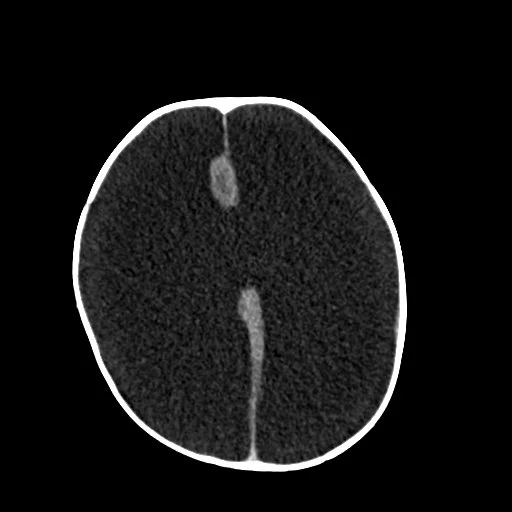

Agenesis of the Corpus Callosum

• Corpus callosum formation

• Forms from front to back

• Rostrum is last thing to form

• Partial agenesis (some corpus callosum is present) or complete agenesis

• Corpus callosum does not develop

• Cingulate gyrus typically will not form either and therefore the more peripheral brain gyri will extend from ventricles to skull

• Bundles of Probst

• White matter bundles that normally would make up the corpus callosum but not just go linearly along the lateral ventricles

• Classic findings

• Racecar sign appearance of ventricles (does not look like racecar)

• Longhorn cattle appearance of ventricles (actually kind of looks like this)